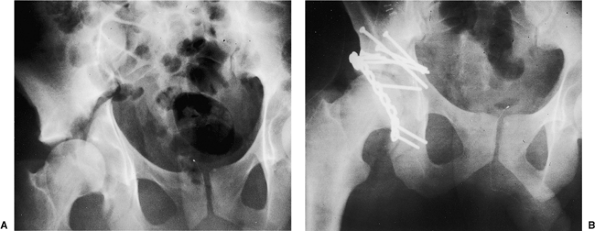

![]() |

|

Figure 43.1. The extended iliofemoral approach for exposure of a comminuted left both-column acetabular fracture. (i) Femoral head. (ii) Abductor muscles and tensor fascia lata. (iii) Schanz pin in greater trochanter parallel with femoral neck.

Figure 43.2. A 28-year-old man with right transtectal ischial T-type acetabular fracture. A. Preoperative AP pelvis. B. Postoperative AP pelvis.